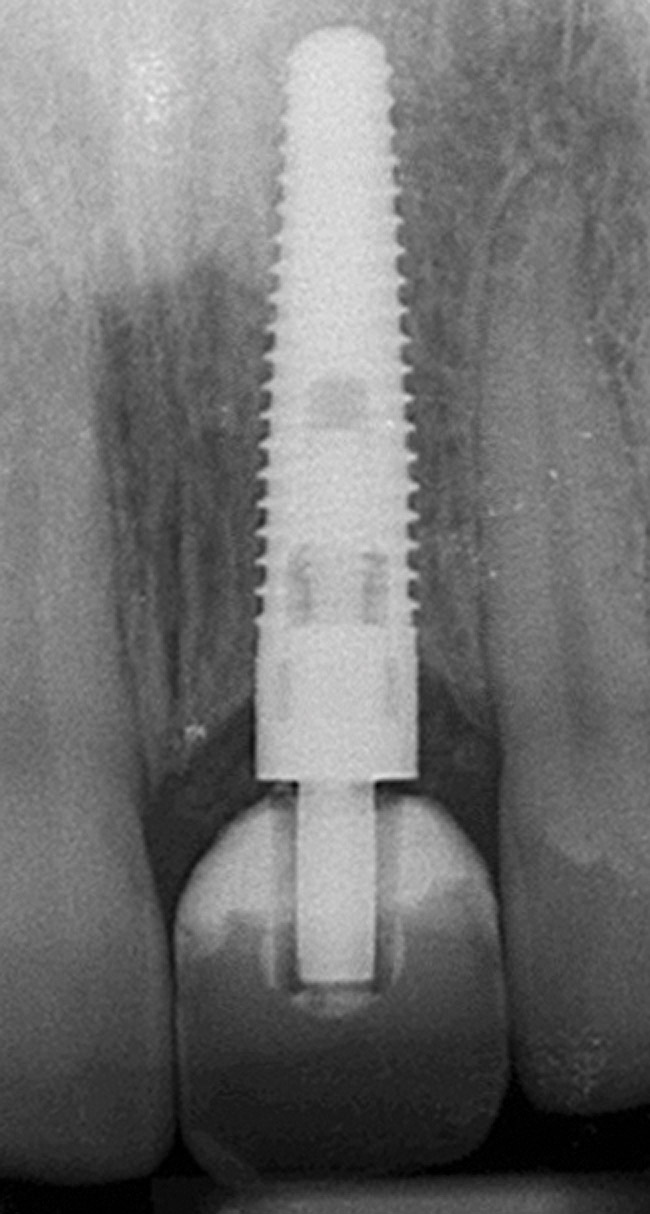

Six months later, the periodontist prepared osteotomies and placed three 3.25-mm x 13-mm implants using a vacuum-formed surgical guide fabricated by the restorative dentist (using a cast of the provisional bridge as a guide, as described by Block et al16); healing abutments were placed simultaneously. A post-implant radiograph confirmed good implant alignment with the pontics of the provisional from teeth Nos. 22 through 28 (Figure 6).

Figure 6  Confirmed ideal implant alignment with pontics in provisional bridge from Nos. 22 through 28—post-placement periapical view.

Figure 6